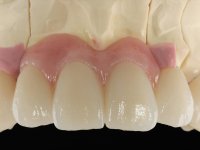

In view of the clinical situation, oral rehabilitation was proposed to improve the aesthetic appearance, but also to solve the lack of posterior teeth, seeking a functional and aesthetic rehabilitation. The plan included replacing the metal-ceramic bridge by a bridge with Zr infrastructure coated with coronary and gingival ceramics. The edentulous area of the first quadrant would be rehabilitated with 2 implants and a bridge of two elements. It was intended with this treatment plan, to recover the vertical dimension of the occlusion and to reshape the dental anatomy, thus creating a more natural aesthetic appearance.

Alginate impressions were made at both arches arcades, accompanied by intermaxillary registration relations and collecting information with facial bow facial bow. In the laboratory, a provisional bridge with 13 elements in autopolymerizable acrylic was built, in which a metallic reinforcement was included. Teeth 1.7 / 1.4 / 1.3 / 2.2 / 2.3 / 2.4 and 2.6 were used as pillars. The metal-ceramic bridge was removed after performing longitudinal cuts with diamond burs. The dental abutments were reprepared and the temporary bridge was relined in the mouth with self-curing acrylic. After confection of the provisional bridge, a gingival epithesis was made using composite resin with gingival tonality in order to function as a mock-up, which allowed the patient to preview the possibility of using gingiva shade ceramics in the final work. This option was approved by the patient. Subsequently, the placement of two implants in the first quadrant was planned and executed. The provisional monoblock was removed for placement of the implants, and after surgery was again cemented provisionally. After the osseointegration period, the impressions were made to the maxilla. In the anterior zone, impregnated gingival retraction cords were used, and in the posterior areas, kaolin paste was used. Implant printing utilized the open tray technique. The printing material used was soft and regular putty addition silicone, both fast-setting. In the laboratory, the model of provisional restorations and the gingiva epithesis mock-up served as orientation for waxing the infrastructure. The plaster work model and the waxing of the infrastructure were placed in a laboratory scanner and yielded a digital work model, in which the scanning of the waxed infrastructure was superimposed. This overlay facilitated the CAD design of the Zr infrastructure. Subsequently, the CAD drawing for a CAM milling process provided the Zr pieces. The infrastructure was pigmented with a pinkish coloration, which favors the subsequent placement of gum shade ceramic. During the modeling of the infrastructure, the need to increase the occlusal wear on tooth 1.4 was detected. This was done in the real working model cast and an acrylic wear control guide was created, which accompanied the proof of the infrastructures. Corrective wear and Zr parts test were performed in mouth. During the test, the color choice of the gum shade ceramic was reassessed. The treatment was finished in the laboratory, and after approval by the patient, was definitively placed in the mouth.